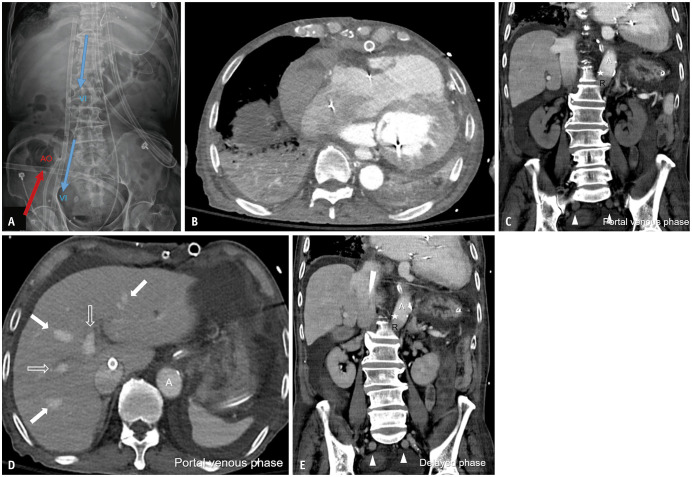

Contrast-Enhanced Abdominopelvic CT After Peripheral Venoarterial Extracorporeal Membrane Oxygenation.

Korean Journal of Radiology Pub Date : 2025-07-01 Epub Date: 2025-06-10 DOI:10.3348/kjr.2025.0256

Eun Sun Choi, Jong Keon Jang